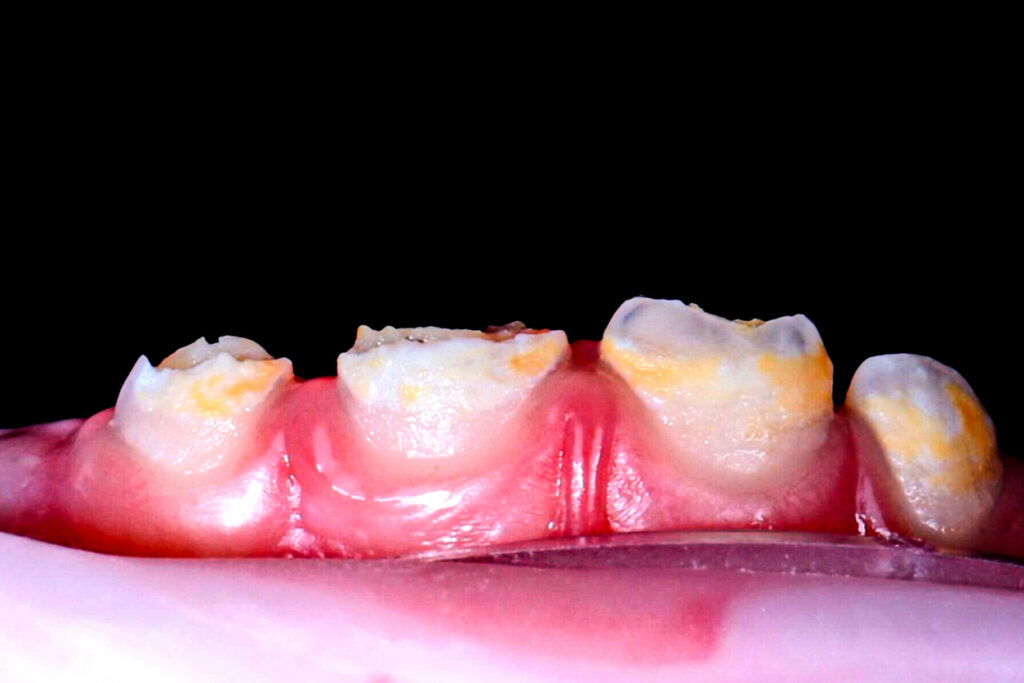

Manifestaciones clínicas de la hipoplasia dental

Los hallazgos más comunes incluyen:

- Surcos horizontales o verticales en el esmalte.

- Fosetas puntiformes o irregulares.

- Áreas lisas sin esmalte en defectos más severos.

- Coloración alterada: blancuzca, amarillenta o parda.

- Predisposición a caries y la sensibilidad dental.

Estas alteraciones pueden afectar de forma localizada (por ejemplo, en un incisivo o molar específico) o generalizada, comprometiendo la estética y función.